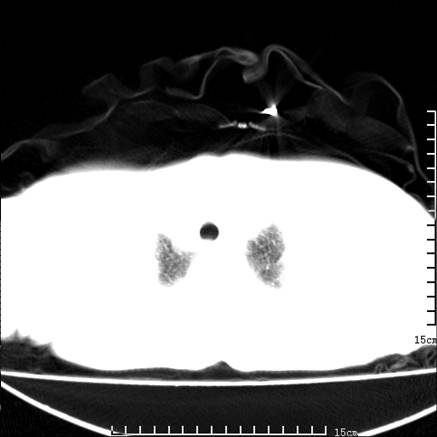

女,王某,58岁,咳嗽三个月余,基层医院二个月前诊为肺结核,用抗结核药二个月无明显疗效。

心包积液致肺瘀血.右侧周围型肺癌伴肺内转移,中间裂积液,叶间胸膜肥厚.右上肺大泡,右侧胸膜肥厚.

双肺继发型tb,心功能不全并肺淤血、心包、双侧叶间裂积液,肺大泡,右下胸膜肥厚钙化。